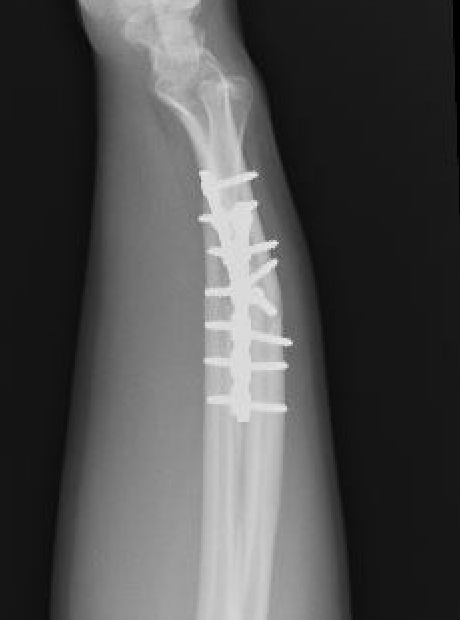

Radial malunion / Non anatomical ORIF of BBFF

Radial malunion after ORIF of BBFF

Etiology

Non operative management of BBFF

Non anatomical ORIF of BBFF

Bone loss radius

Radius short

Lengthening radius difficult

Ulna shortening

Radius angulated / rotated

Radial osteotomy

TFCC repair +/- TFCC reconstruction